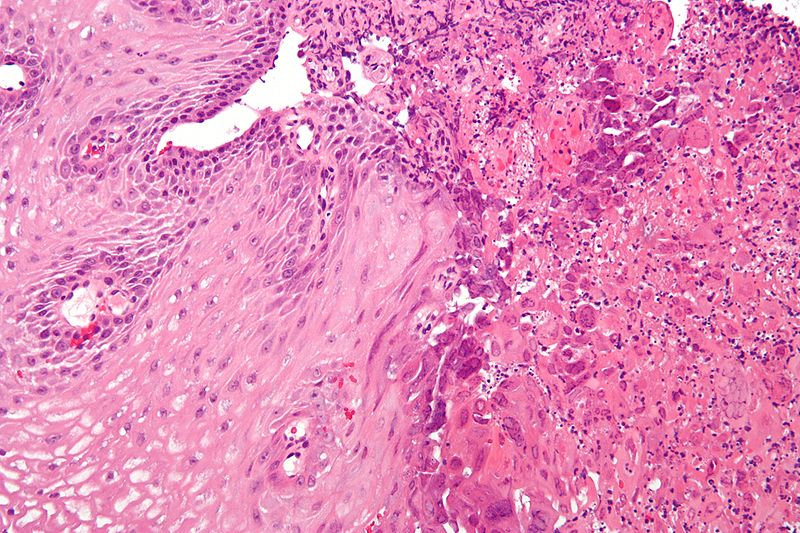

• Эзофагогастродуоденоскопией. Этот метод является золотым стандартом в диагностике эзофагита. С помощью эндоскопа проводится осмотр стенок пищевода, желудка и двенадцатиперстной кишки. В некоторых случаях врач проводит биопсию пищевода, отсекая небольшой образец слизистой оболочки через эндоскоп. Этот образец отправляется на гистологическое исследование.